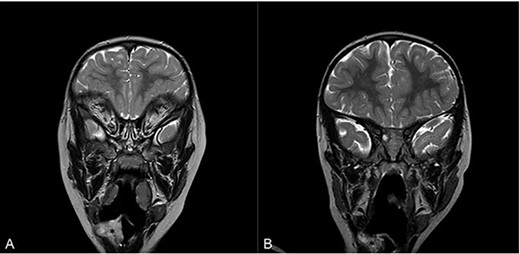

Flexible nasoendoscopy found a 1 × 1.5 cm sessile mass adjacent to the epiglottis, also seen on magnetic resonance imaging (MRI) (Fig. 1A). The patient was referred to a tertiary Ear, Nose and Throat (ENT) centre and admitted to the paediatric intensive care unit.

Magnetic resonance imaging (MRI) of head and neck with contrast in sagittal view on admission (A) and at 16 months follow-up (B). Asterisk denotes area of interest.

Sixteen months after the second debridement, the patient had a largely asymptomatic airway, stable disease on MRI scans (Fig. 1B) and no signs of significant lesional growth or airway obstruction on repeat microlaryngoscopy (Fig. 2C). At 30 months follow-up, imaging shows the neurofibroma to have mildly increased in size but there are no significant respiratory symptoms and no functional impairment.